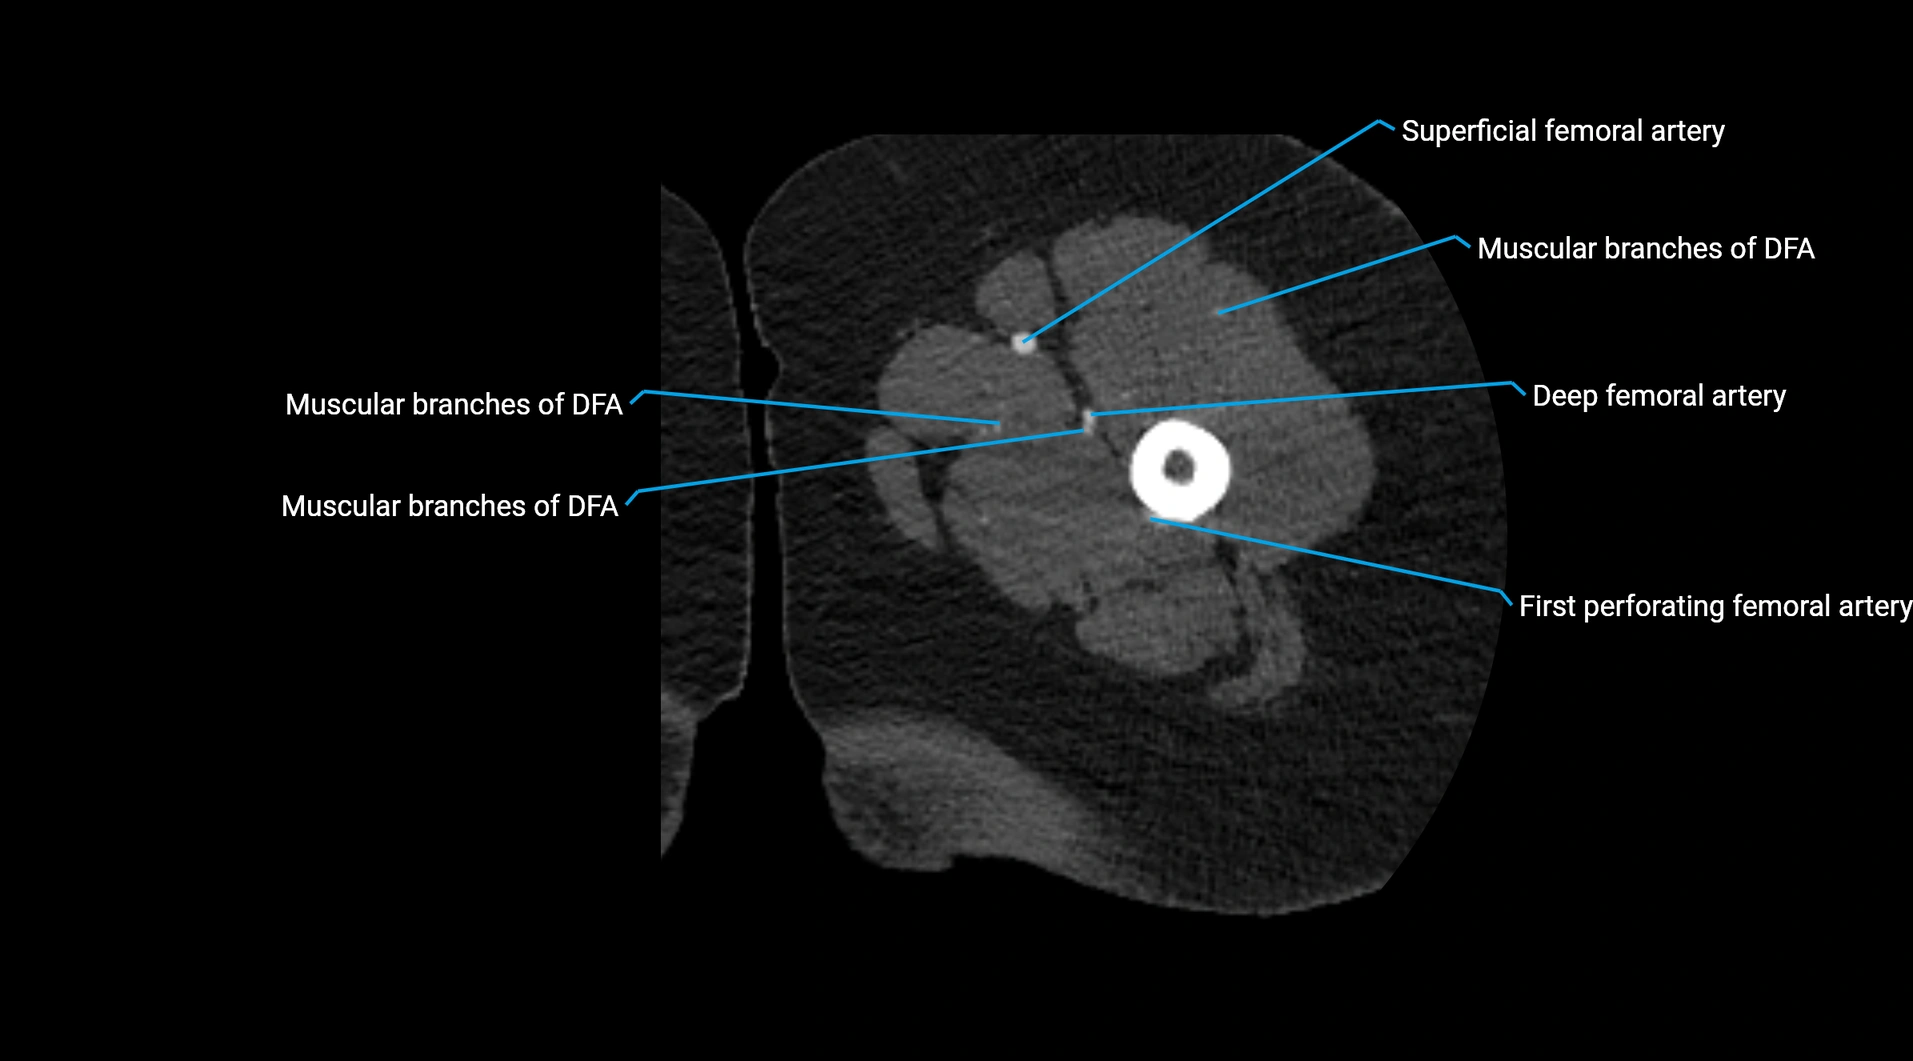

Contrast-enhanced CT (CTA):

• Gold standard for abdominal aortic imaging

• Provides excellent detail of lumen, wall, aneurysm, thrombus, and branch vessels

• Multiplanar and 3D reconstructions help in aneurysm measurement, stent graft planning, and dissection evaluation

• Detects acute rupture, traumatic injury, or occlusion with high sensitivity